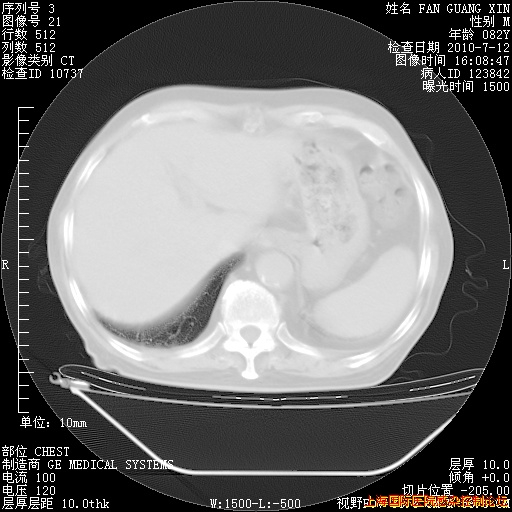

今天复查CT

今天CT

整整相隔30天的肺部CT好像有所好转啊。甲强龙减量第3天,需要观察体温。

海管,自昨日你和我通完话后,不知您岳父消化道症状有无缓解?体温怎样?阅读7.12日胸部ct,个人认为目前激素治疗是有效的,甲强龙减量是适宜的。因在抗痨治疗,需密切观察肝功、肾功能和血常规。不过,老年、长期住院和大量使用激素,很担心菌群失调发生